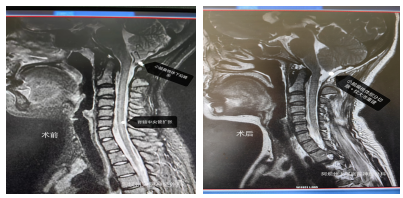

其中,两位女性患者的手术案例尤为引人关注。一位46岁的壤塘籍女性患者,因头昏痛伴胸前区疼痛2年就诊,诊断为Chiari畸形II型。另一位32岁的色达籍女性患者,因头颈部不适伴四肢麻木2年就诊,同样被诊断为Chiari畸形II型。两位患者均接受了环枕畸形减压术+脑脊液漏修补术+小脑扁桃体部分切除术+枕大池重建术,术后恢复良好。(病例1:女性,46岁患者,壤塘籍,“因头昏痛伴胸前区疼痛2年”,诊断:Chiari畸形 II型。实施手术:环枕畸形减压术+脑脊液漏修补术+小脑扁桃体部分切除术+枕大池重建术。

术中手术照片:

病例2:女性,32岁,色达籍,因“头颈部不适伴四肢麻木2年”,诊断:Chiari畸形 II型,实施手术:环枕畸形减压术+脑脊液漏修补术+小脑扁桃体部分切除术+枕大池重建术。)